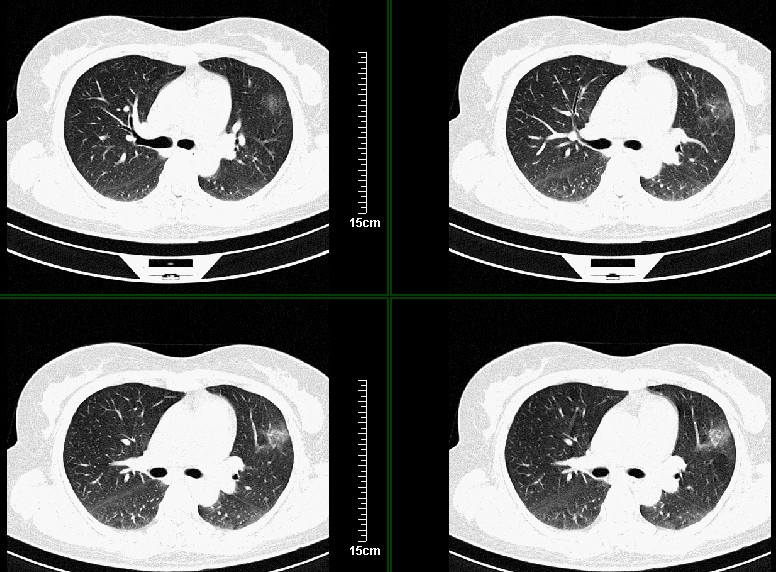

一周之后 复查结果 5mm扫描 40多岁 我们医院的护士

左肺上叶肿块,肺窗周围有“晕征”,纵隔窗有毛刺,临床资料???只能考虑占位???

第八幅图像,典型毛刺,像日本鬼子的膏药军旗一样,一看就不是个好东西

病灶分明小多多了